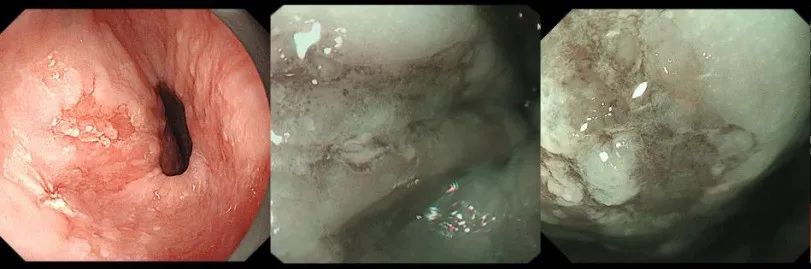

在科室何林方主任的带领下,科室常规开展无痛胃肠镜、精查染色胃肠镜、超声胃肠镜、色素放大内镜、窄带成像技术(NBI)、磁控胶囊胃镜、胶囊小肠镜等检查,能开展胰胆疾病的内镜下治疗(ERCP):包括十二指肠乳头肌切开(EST)、胆管取石术、胰胆管支架置入术、内镜下鼻胆管引流术;食管胃底静脉曲张套扎、硬化剂、组织胶注射治疗;内镜下的粘膜剥离术(ESD)、内镜黏膜下切除术(EMR)、经口内镜食管括约肌切开术(POME)、经内镜黏膜下隧道肿瘤切除术(STER)、空肠管置入术;痔硬化、套扎治疗;胃造瘘(PEG)、食管、肠道支架置入;食管狭窄扩张术,食管瘘口封堵术;经颈静脉肝内门-体分流术(TIPS)、超声内镜引导下的胃曲张静脉精准断流术(EUS-SVD)、内镜超声引导下胆道引流术(EUS-BD)、内镜下幽门括约肌切开术(G-POME)、经内镜逆行阑尾炎治疗术(ERAT)等国际最新内窥镜微创治疗。